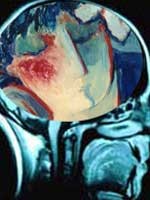

Scan Otak Bantu Baca Pikiran